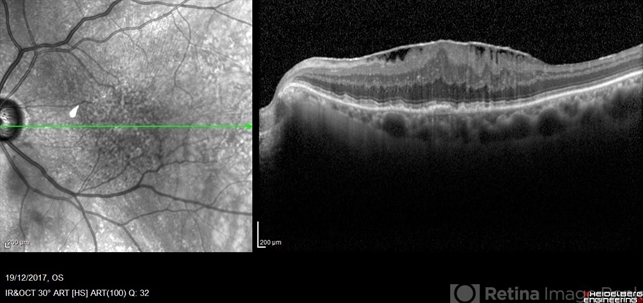

- epiretinal membrane (ERM), macular pucker

Optical coherence tomography system

Heidelberg Spectralis - Description

- SD-OCT showing an epiretinal membrane causing significant distortion of the macular architecture.